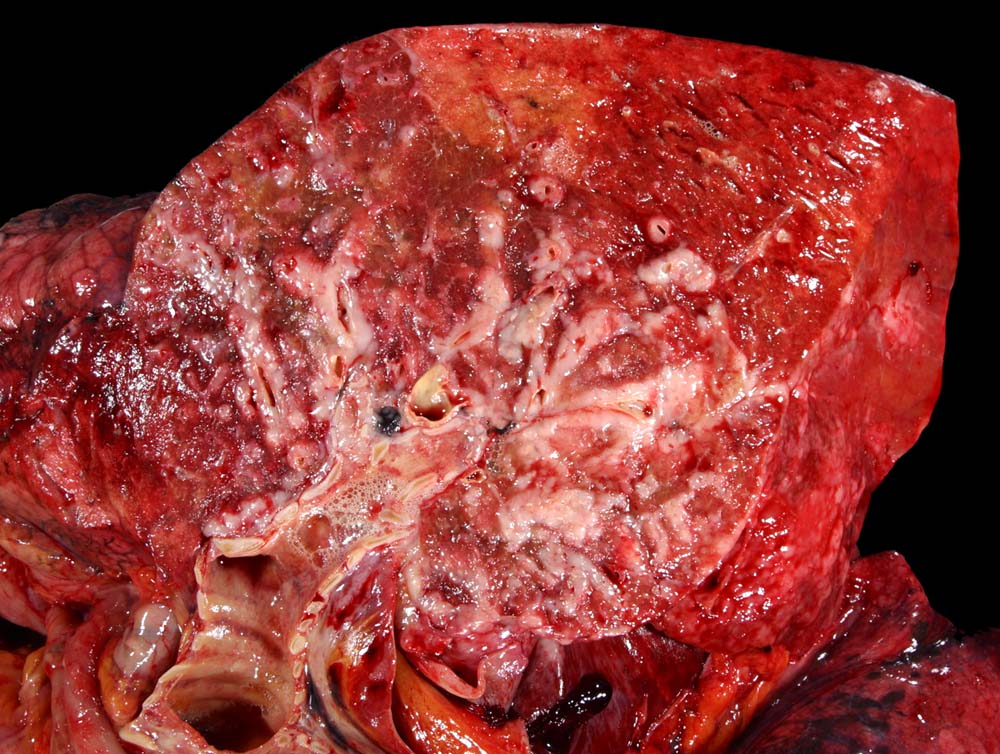

Das metastatische Wachstumsmuster von primären Bronchuskarzinomen und extrapulmonalen Tumoren innerhalb der Lunge ist variabel. Hämatogene Metastasen imponieren makroskopisch als multiple scharf begrenzte rundliche Knoten in allen Lappen meist in peripherer Lage. Der metastatische Befall von Lymphknoten kann durch direkte Tumorinfiltration durch den Primärtumor erfolgen (=per continuitatem) oder über die Lymphgefässe. Bei einer ausgeprägten lymphogenen Tumorausbreitung erscheinen subpleurale mit Tumor gefüllte Lymphgefässe makroskopisch als prominente weisse Streifen. Mikroskopisch lassen sich Tumorinfiltrate in peribronchialen und perivaskulären Lymphgefässen nachweisen (=Lymphangiosis carcinomatosa). Hepatozelluläre Karzinome metastasieren typischerweise in Form von Tumorembolien (> 1279) hämatogen in die Lunge.

• Sternförmiges Karzinom mit zentraler Vernarbung mit reichlich schwarzem Anthrakosepigment.

• Das Karzinom ist aufgebaut aus tubulären und kribriformen Drüsen.

• In den sternförmigen Ausläufern finden sich erweiterte Endothelausgekleidete Lymphgefässe in der Nachbarschaft von Blutgefässen.

• Die erweiterten Lymphgefässe enthalten solide Tumorzellaggregate.